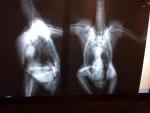

Рентген post-22850-1428692655_thumb.jpgpost-22850-1428692676_thumb.jpgpost-22850-1428692694_thumb.jpg